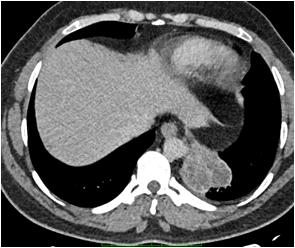

histopathology or polymerase chain reaction in a Patient with a clinical diagnosis of Invasive Mucormycosis. Cases were considered COVID-19 associated if the patient received a positive Reverse Transcription Polymerase Chain Reaction or Antigen test result for SARS-CoV-2 during the 60 days preceding the mucor diagnosis1.” Every patient is evaluated at presentation with detailed history, Clinical examination, ENT, Ophthalmic and Neurological examination to assess the extent of disease. Patients’ occupational history, personal habits, Socio-economic status (Modified B G Prasad Scale), prior treatment, vaccination status & COVID status were recorded at admission. Patients with pre-existing Facial Nerve palsy due to other known causes like cerebrovascular accident, non-covid intracranial, temporal bone, parotid pathology were excluded. Facial soft tissue involvement if mimicking Facial Palsy was also excluded. Facial Nerve function assessment was done in detail. It was first subdivided into upper and lower Motor Neuron type of deficit. LMN lesions were further graded by the House Brackmann Scoring System. Topo-diagnostic tests like Schirmer test, Stapedial reflex test and Taste sensation were assessed as far as practicable. Diagnostic Nasal Endoscopy (DNE) and Radiological assessment (Computed Tomography and Magnetic Resonance Scan of Head, Neck and Orbit) was done. Patients undergoing surgical debridement and those considered for conservative management were followed up at three months to check for change in the state of Facial Palsy. All interventions were done maintaining institutional and ICMR COVID protocol.

Radiological assessment in the form of Magnetic Resonance Imaging and Computed Tomography of the diseased site was done. Contrary to the clinical presentation, all of the patients (100%) had Nose and Para nasal sinus involvement. Orbit was involved in 72.72% of patients. Pterygopalatine fossa involvement and intracranial disease extension was found in 54.54% of the patients respectively. None of the patients had infra-temporal fossa and temporal bone involved by Mucor.

Route of disease spread was classified (based on clinico radiological findings) as Superior route if there were features of Nose and Skull Base involvement. Patients having Nose and Oral cavity involvement without involvement of the Skull base were considered as Mucor with Inferior Route of spread. It was found that 9 out of 11 patients of CAM with Facial Nerve Palsy had features suggestive of Superior route of Mucor spread.

Fig 1Fig 2Fig 3 Fig 4Fig 5

Figs 1-5 — Photographs of patients suffering from Post COVID Mucormycosis with new onset Facial Nerve Palsy